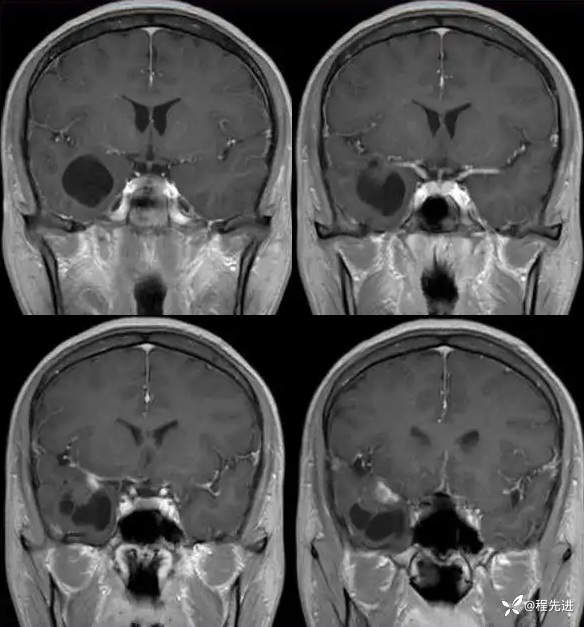

现病史:患者10天前无明显诱因突发四肢抽搐伴意识障碍,发作时口吐白沫,牙关紧闭,大约5分钟后患者清醒,醒后不能回忆发作时情况,查头颅MRI检查提示右侧颞叶占位。门诊拟“继发性癫痫”收住入院。患者病程中无明显头痛头晕,食纳睡眠可,大小便可,体重无明显变化。

T1:

T1增强: